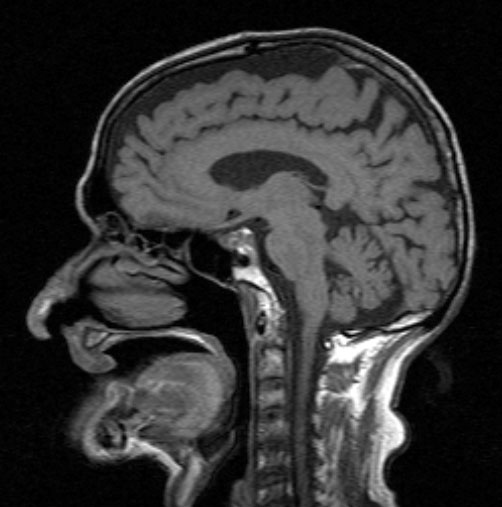

Esowatchwikilinks:

In der Harnblase bildete sich Urin, der, nachdem man dies Jani mitteilte verschwand. Im Artikel schrieb ich bereits, dass Jani sich oft mit dem Rücken zur Videokamera drehte. Die Videos sind bei YT zu sehen. Denkbar und naheliegend dass er heimlich sein Urin (etwa 0,1 L) trank. Im Darm wurde im MRT festgestellt, dass sich dort Kot befand, sowie Darmgase. Die MRT-Bilder sind im Internet online.

23. Welches Loch in seinem Gaumen bitte ? Das ist doch nun kinderleicht festzustellen, das kann jeder Anfänger in HNO, sogar Medizinstudenten nach dem Anatomiekurs. Es ist aber noch besser: es liegen nämlich im Internet offen die MRT-Bilder von Jani vor. Sieht man die sich an, so zeigt sich, dass sowohl der harte Gaumen, Boden der Nasenhöhle wie auch die Uvula völlig intakt sind. Ich habe Esowatch den Link genannt, vielleicht laden die das MRT-Bild noch hoch, dann kann jeder nach Löchern suchen.

40. Das MRT-Bild von Mataji (Prahlad Jani) ist jetzt hochgeladen worden:

https://www.psiram.com/de/images/7/76/MRT-Mataji.jpg

Es gibt ansonsten nur noch drei weitere Bilder vom seinem Schädel im Internet. Es sind drei horizontale Schnitte, die unauffällig sind und wohl gemacht wurden um im Falle von Komplikationen zu Vergleichszwecken zur Verfügung zu stehen.

Das Bild hier zeigt keinerlei Öffnung im harten oder dahinterliegenden weichen Gaumen. Allerdings zeigt das Bild nur die Medianebene, das heisst (je nach gewählter Schichtdicke) wäre es theoretisch möglich dass sich rechts oder links seitlich noch ein Loch verbirgt. Da die Untersucher behaupten, er hätte ein „Loch im Gaumen“ bleibt unverständlich warum sie nicht die Schicht zeigen, die das Loch zeigen.